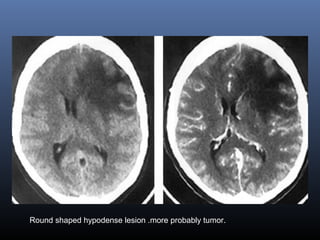

STROKE MIMICS

Stroke

1. Sudden onset

2. Gray &White matter

involved

3. Wedge shaped

4. Typical vascular

distribution

Tumor

1. Gradual onset

2. Tends to spare cortex

preferentially involves white

matter

3 .Round or infiltrating

4. Not confined to a specific

vascular territory

Round shaped hypodense lesion .more probably tumor.